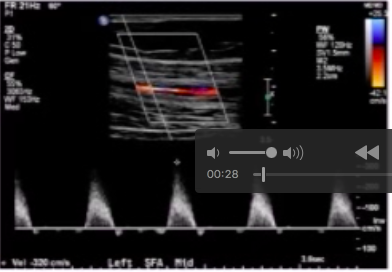

Pt w/ claudication at rest has arterial DUS image shown below. Note that PSV proximal to popliteal lesion is 60 cm/s.

How will you report the findings in the images?

75-99% stenosis in distal popliteal artery

lesion in distal popliteal artery w/ elevation of PSV > 4x ⇒ 75-99% stenosis